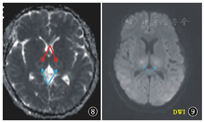

弥散加权成像(diffusion-weighted image,DWI)较传统序列能更好地反映病理变化,DWI其表观弥散系数图(apparent diffusion coefficient,ADC)能更好地反映出来。在急性期典型病例丘脑损伤的表现可用具有特征的三色板模式图形象地将其原理表现出来(图7),丘脑中央部(图7A,下同)显示为较正常脑组织高的ADC值,表示出血坏死;A周围的ADC值低(图7B),表示细胞毒性水肿;损害灶的外围部(图7C)有较中央更高的ADC值,为血管源性水肿[22]。

注:ADC:表观弥散系数;A显示为较正常脑组织高的ADC值,表示出血坏死;B表示比A低的ADC值,为细胞毒性水肿;C表示比A更高的ADC值,为血管源性水肿